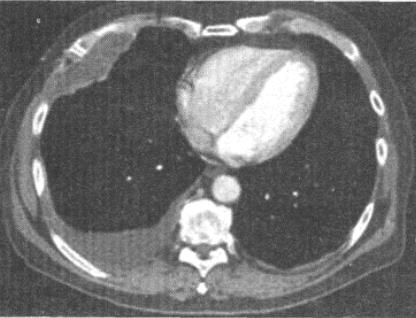

- 单项选择题 患者男,70岁,以前是管道安装工,有石棉接触史,也有很长的吸烟史,结合CT检查,最可能的诊断是()。

B、胸膜间皮瘤

- B